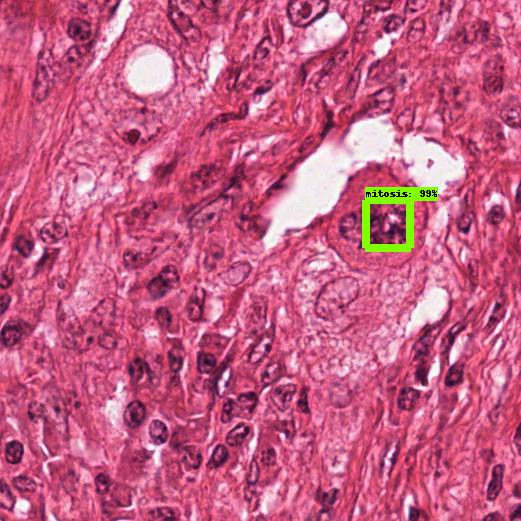

See Fig. 3 for sample detections.